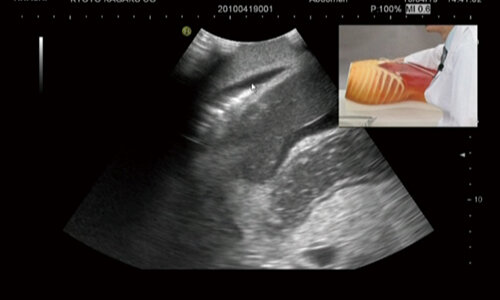

【Click Figure for video show - US5:FAST/Acute Abdomen Phantom 】

The FASTER/ER FAN phantom was developed for ultrasound examination directed at identifying the presence of free intraperitoneal or pericardial fluid in traumatic patients. This phantom allows for the detection of possible causes of shock such as mass hemothorax, intraperitoneal hemorrhage or cardiac tamponade.pdf

| Left upper abdominal bleeding (Hemothorax) | right upper abdominal bleeding (Hemothorax) | |

| Cardiac tamponade | Right upper abdominal bleeding (Morrison's pouch) |